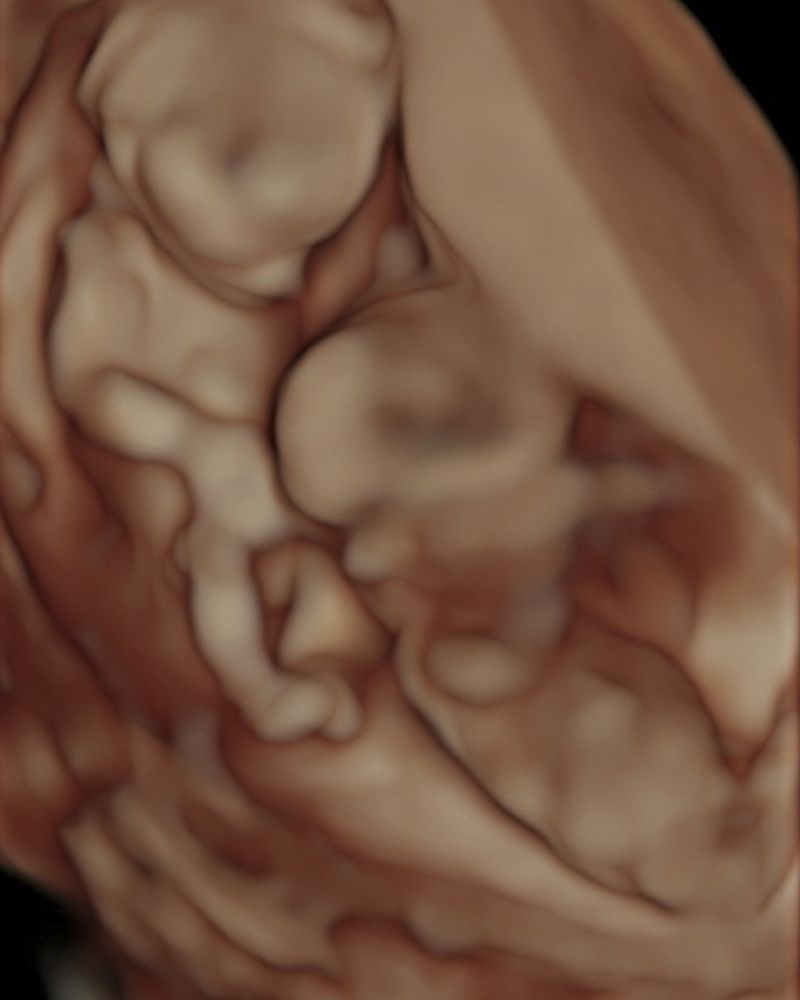

At the moment of fertilization, the egg releases chemical signals that attract the ideal spermatozoid, the most compatible, to its center. Over the next two weeks, by some inexplicable chance, it’s possible that the fertilized egg will divide into two exactly equal zygotes, and it’s at that moment that the gestation of monozygotic twins will begin, two beings with the same DNA chain and genetic information.

In Las dos hebras, I combined archival images from the study of genetics, diagnostic images of my genes and those of my twin, photographs of monozygotic twins, microscopic photographs that were taken in science and fertility labs, and images with poetic symbols that, as a whole, seek to establish contact with other people, whether twins or not, who may arrive at a place to question what in this alphabet, reflexive code, or mirrored code makes us human.